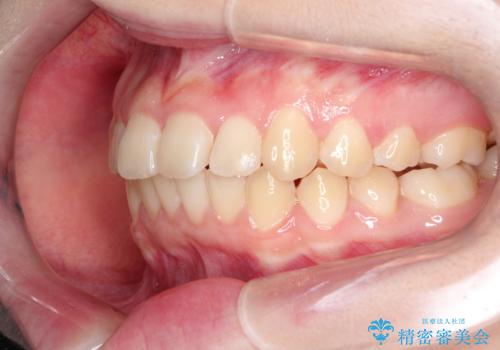

受験生ということもあり、来院頻度が少ないマウスピース矯正で治療が終了できたことに満足いただけました。

上下の正中が一致していませんが、受験を控えているためご本人の希望もあり、いったん終了とさせていただきました。

治療の中断・再開が容易なのもインビザライン治療のメリットといえます。